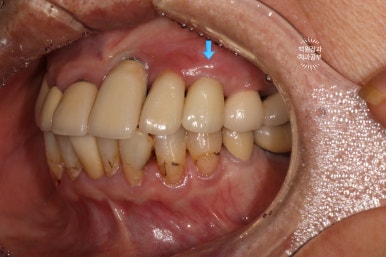

보시면 이가 없던 자리에 임플란트 두개가 생겨 있는 것을 보실 수 있습니다.

발치 동시 임플란트의 또 다른 특징으로, 대부분 임플란트 2차수술을 하지 않습니다.

왜냐~ 이를 뽑으면서 임플란트를 바로 심기 때문에, 잇몸이 비어있는 부분이 있잖아요? ㅎㅎ 그러니 당연히 뚜껑을 껴야한다구요!! 그래서 임플란트 수술이 모두 끝나버립니다.

스트라우만 임플란트를 사용하여 수술하였던 어금니 부위에 임플란트 머리가 제작되었습니다!

상당히 많은 임플란트를 가지고 계시지만, 다행히 그 사이에 예쁘게 쏙 심어내었답니다 :)

약간 생긴게 다른데, 임플란트도 회사마다 보통 약 3-4가지 라인업이 있기 때문입니다. 스트라우만 임플란트의 경우 크게 Standard, BLT, BLX 라인이 있으니 형태가 달라도 놀라지 마세요! 상황마다 용도가 다를 뿐입니다.

어느게 스트라우만 임플란트인지 확인 가능하신가요..? ㅎ

화살표로 표시해놓은 것들이 이번에 새로 임플란트로 채워넣어진 자리입니다!

진짜 깔끔하고 예쁘게 마무리 되어서 너~무 뿌듯합니다 :)